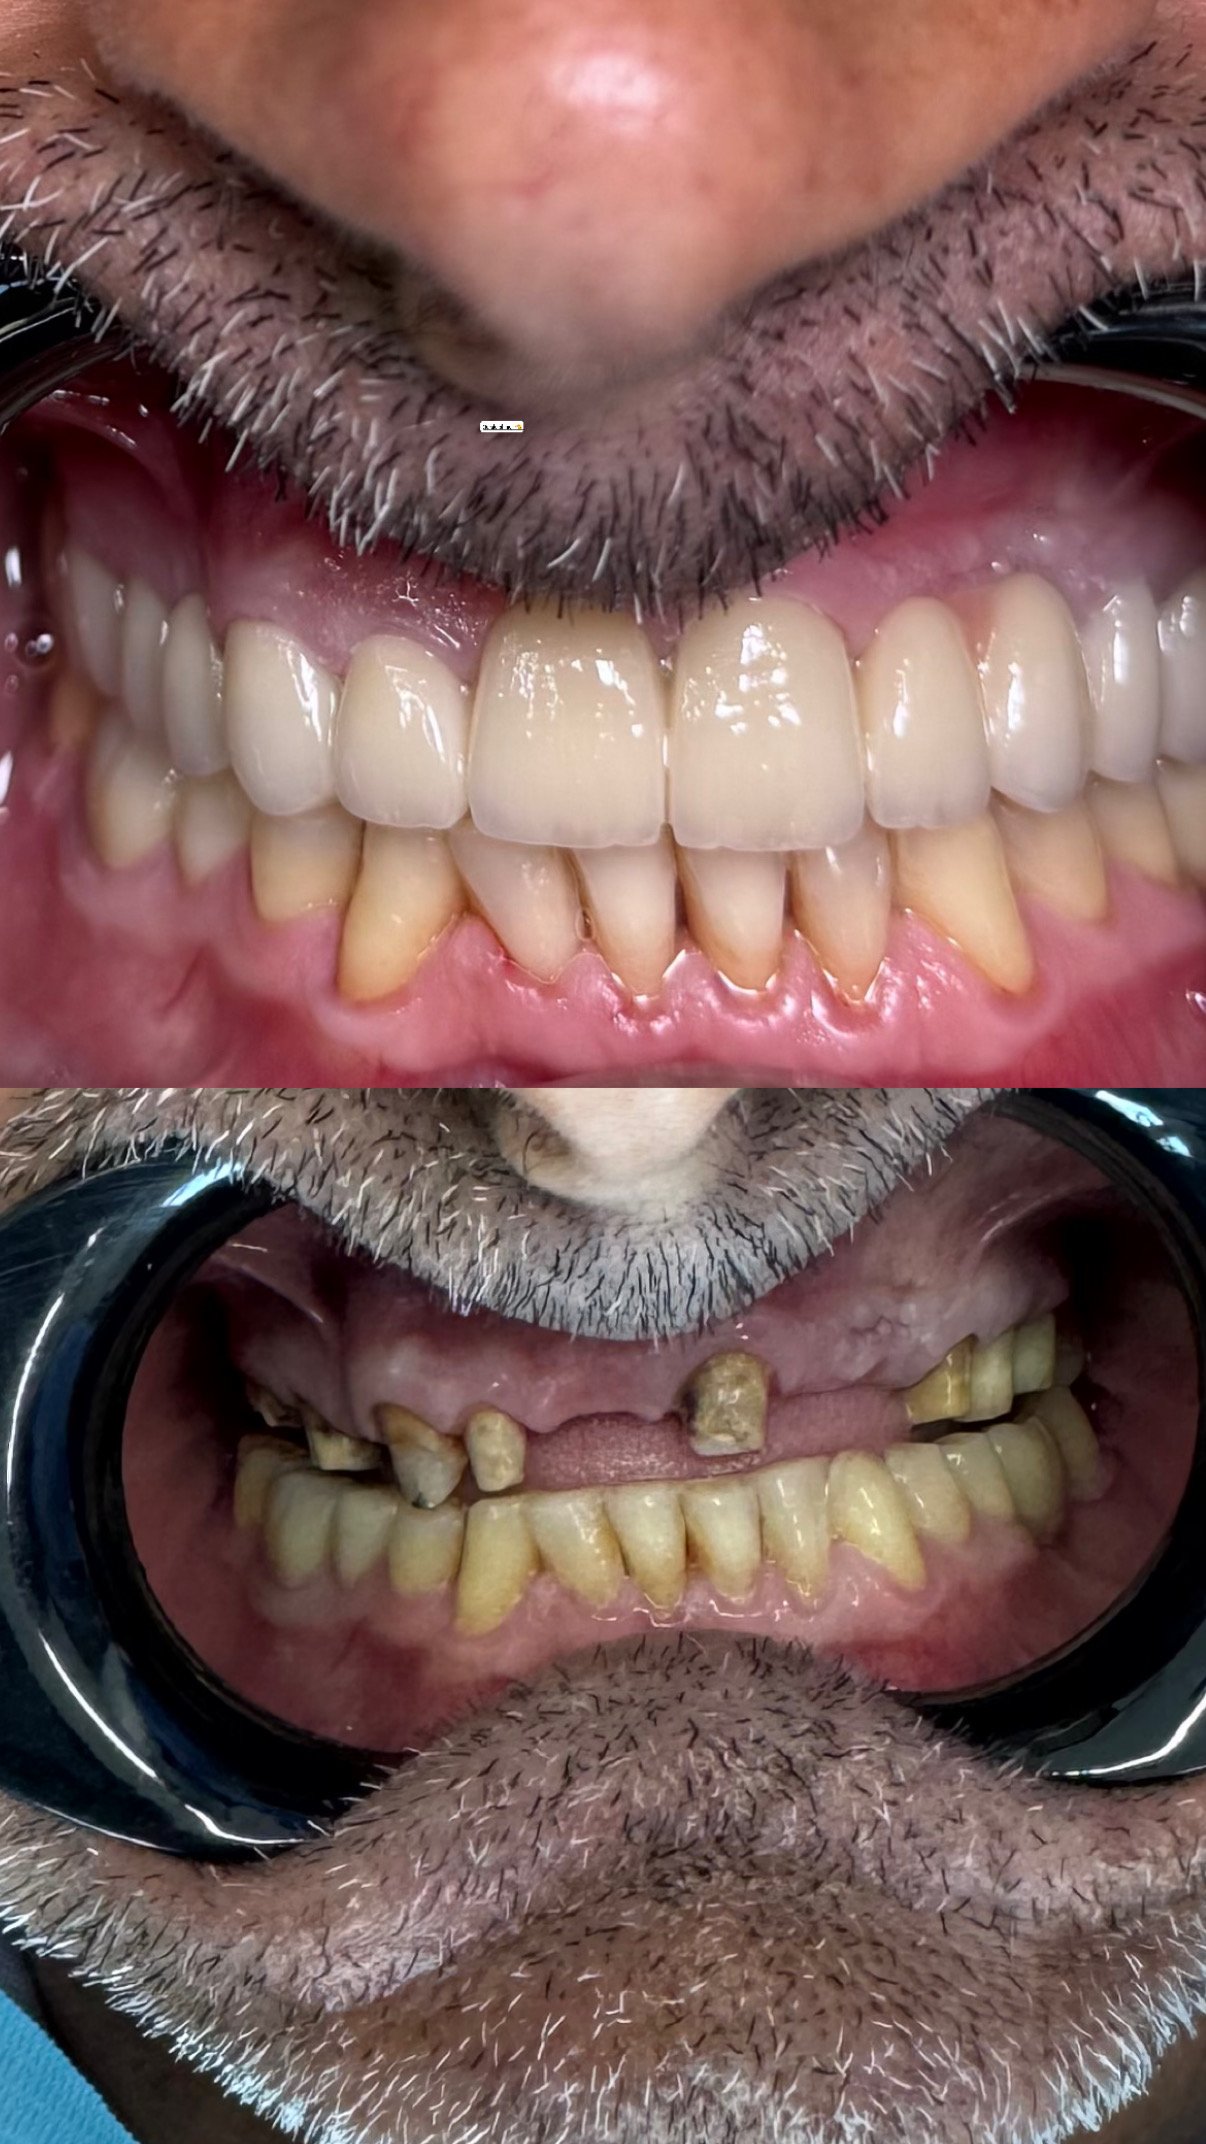

Lavori

Nuove idee

per un sorriso più sano